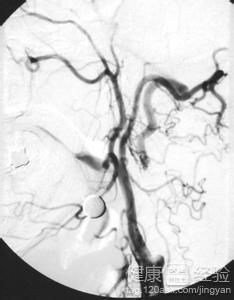

醫生,我想請問一下,我媽媽以前的時候偶爾會有心絞痛的症狀,她經常說胸口很疼,有點喘不上氣,但是很快,休息一下子就好了。也沒有去醫院看。但是她最近心絞痛頻率較高,經常頭暈,家裡人很擔心,我們就去醫院檢查,醫生說腦袋裡有斑塊,那個斑塊能清除嗎?請問怎麼樣才能減少心絞痛呢?要多鍛煉嗎?她應該吃些什麼東西呢?真希望她能快點好,望醫生解答啊,謝謝啦!